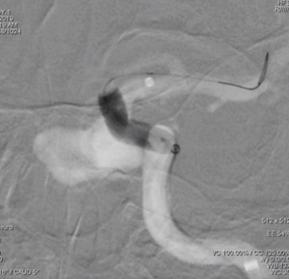

球囊首次扩张,支架展开,首次造影图示动脉瘤近端贴壁不良,有造影剂渗漏至动脉瘤腔内,故再次充盈球囊扩张支架近端。

再行造影见动脉瘤不显影,无造影剂渗漏,血管重建满意。

3D重建图示支架贴壁良好。